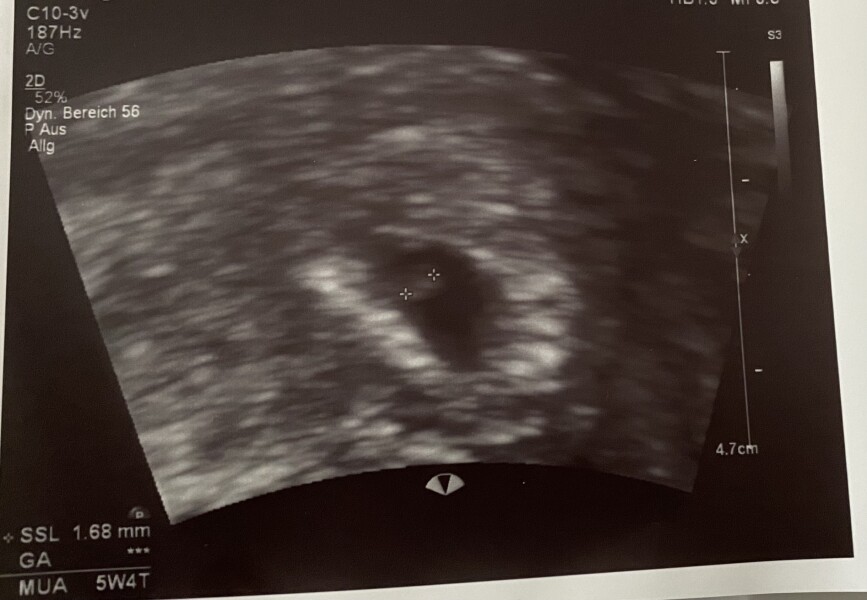

LarasMama · 17/06/2022 13:50

@Juno231 Thank you, dear. I think I’m now 5w4d. Had a scan today, but we couldn’t see the baby or the heartbeat. I know it’s early and my gyno wasn’t too concerned. But somehow I am. When did you first see/hear baby?

LarasMama · 17/06/2022 13:53

Here’s the scan